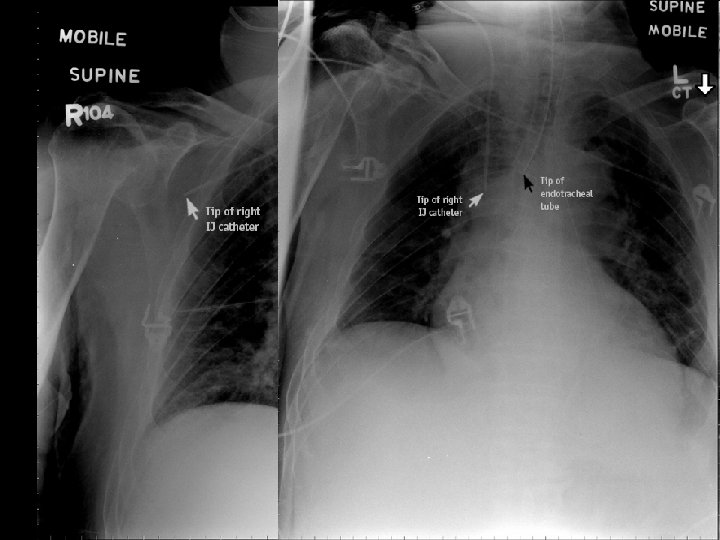

Central venous catheterization • v. jugularis int. • v. subclavia – infraclavicular (less supraclavicular approach) • v. femoralis (urgent approach) • v. axillaris, v. mediana cubiti, v. jugularis ext. • v. umbilicalis (newborns) • complications: infection, pneumothorax, hemothorax, plexus brachialis injury, air embolism

Central venous catheterization • • • permanent venous approach central veins do not collapse during shock monitoring of central venous pressure large volume replacement application of parenteral nutrition application of catecholamines, substances irritating venous wall (cytostatics, glucose), high-osmolar solutions • dialysis

Wrong position of catheter